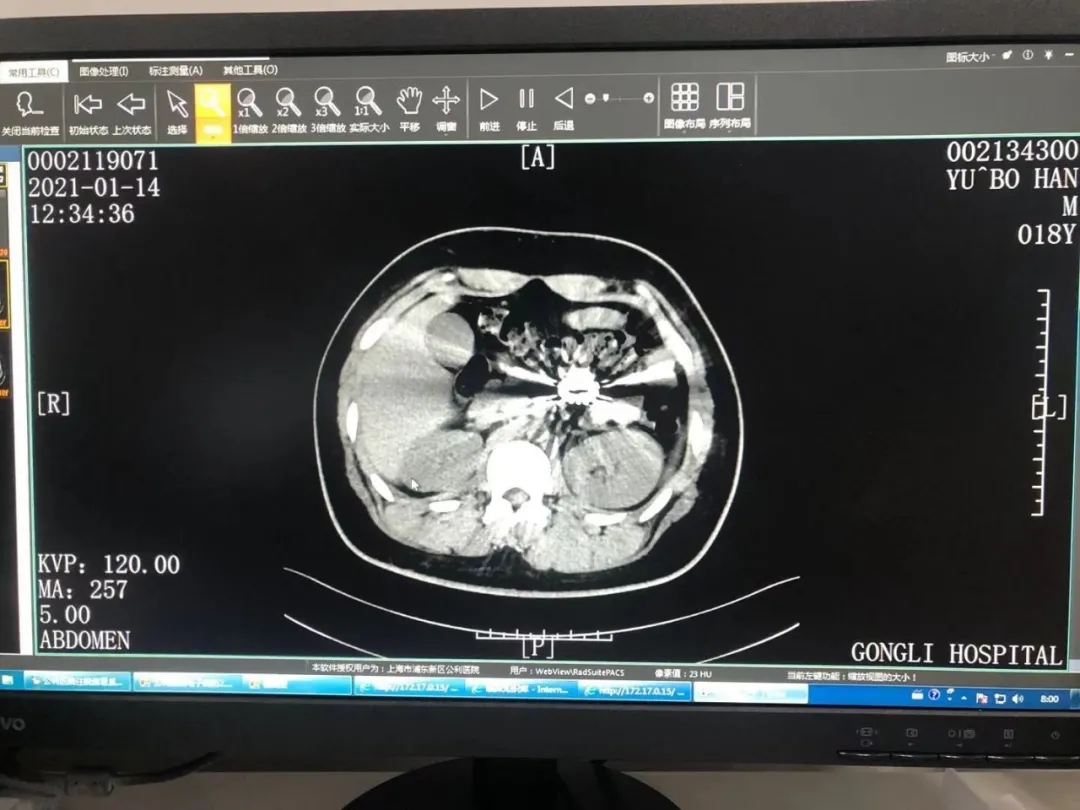

这天,公利医院普外科副主任医师陈志刚接诊了一位外地慕名而来的小患者。家长介绍,两天前,孩子不慎误吞了15颗小磁珠,当地医院曾尝试利用胃镜取出异物,但并未成功,心急如焚的家长赶紧带孩子来到上海就医。陈志刚发现孩子当时没有明显腹痛,当即为其复查了腹部平片和CT,并请影像科业务主任郑海宁一同读片。

郑海宁仔细读片后,发现异物已经进入孩子空肠上段。要知道,这一位置对于内镜来说难以企及,这可怎么办?是保守等待患者自行排出,还是立即手术?